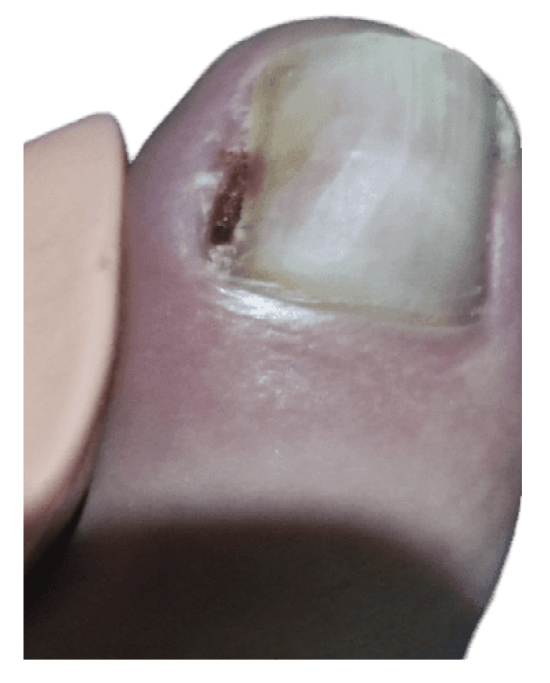

The patient initially showed improvement in pain, although it never completely subsided (Figure 4). She reported recurrence of the nail lesion, which led her to seek a second opinion 6 weeks after the intervention with another podiatrist. This latter podiatrist, on December 27th (Figure 5), performed a bacterial culture of the lesion, which turned out negative, and also evaluated the lesion by ultrasound (without report). On January 13th, the patient underwent surgery using the phenol-alcohol technique on the lateral border of the first toe of the left foot (Figure 6).

Figure 5. 16th week. Negative microbiological culture and sonograhpic assessment (not available).

Figure 6. 18th week. Second intervention by means of phenol-alcohol partial matricectomy.

Within 3 weeks after the third intervention, the patient reported recurrence of the lesion and painful symptoms (Figure 7). The patient decided to attend the traumatology department (February 2023) where an MRI (T2FS and DPFATSAT) was requested. It showed an occupying mass in the lateral third of the first toe with well-defined borders and bone involvement (Figure 8) with the following report: “At the level of the distal phalanx of the 1st toe in the nail region, there appears to be a solution of skin continuity with a heterogeneous, a dense 15 mm x 14 mm collection in the lateral region of the parapharyngeal soft tissues, remodeling the bone and coming into contact with the flexor tendon, which could be consistent with a postoperative abscess/phlegmonous collection. Some bone edema in the distal phalanx is suspected, without completely ruling out incipient osteomyelitis. To be correlated with medical history and surgical protocol performed.”

Figure 7. 21th week. Recurrence of lesion after phenol-alcohol surgery.